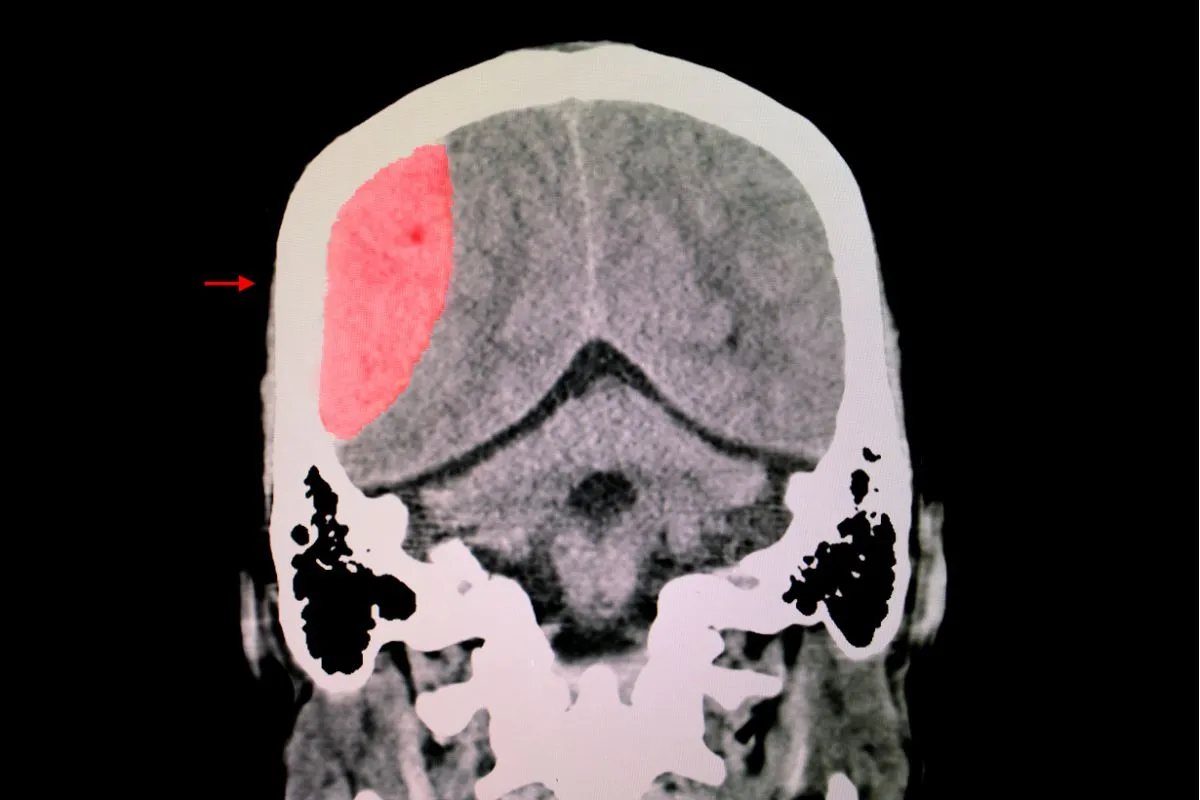

- Brain Blood Flow: SPECT brain imaging played a crucial role in this study, showing significant improvements in brain blood flow after the HBOT sessions. Enhanced blood flow to the brain is often associated with better cognitive function and overall brain health.